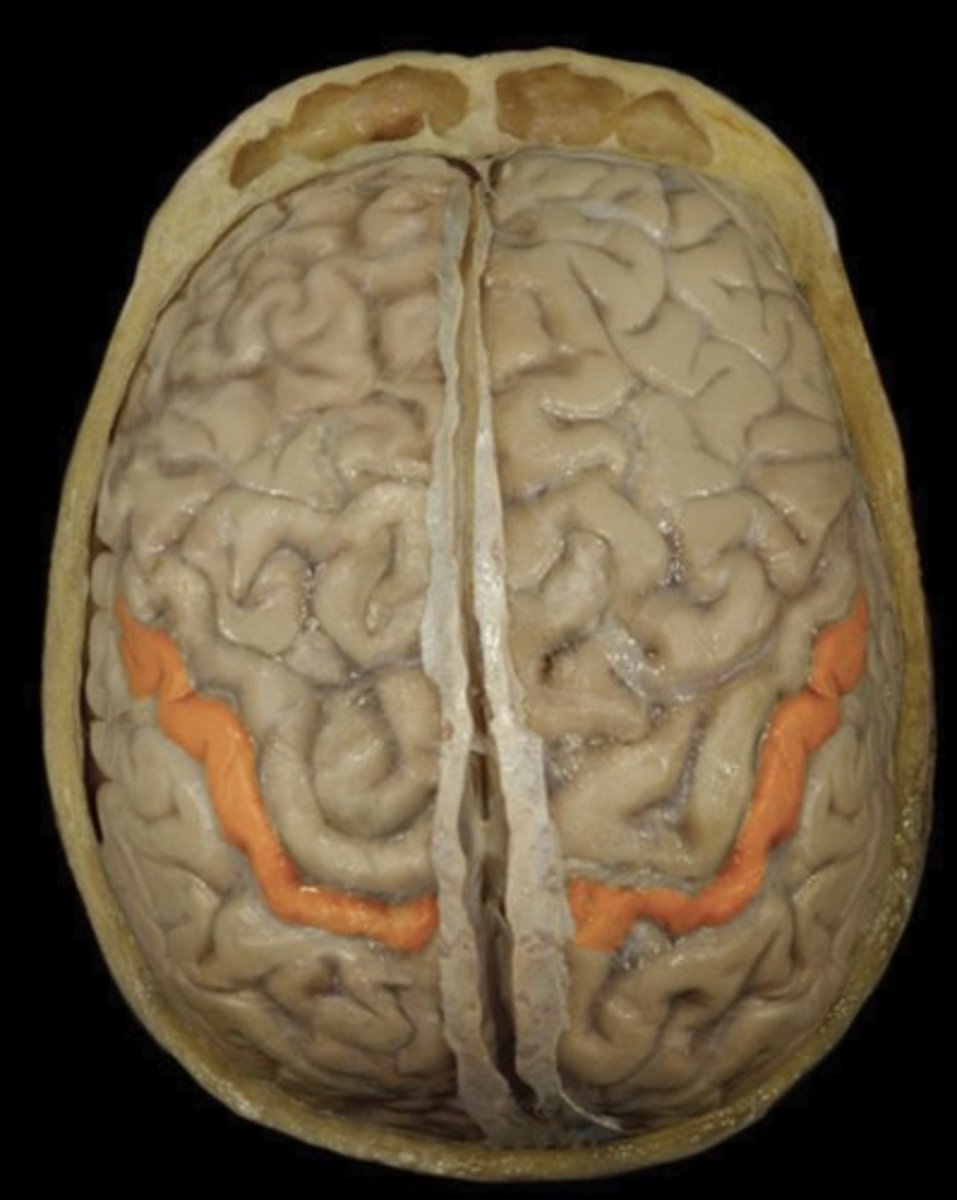

Central Sulcus

Name this structure

Precentral Gyrus (superior view)

Name this structure

Postcentral Gyrus (superior view)

Name this structure

Frontal Lobe (superior view)

Name this structure

Occipital Lobe (superior view)

Name this structure